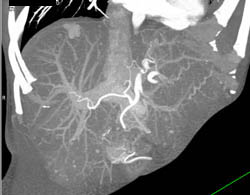

Cholangiocarcinoma